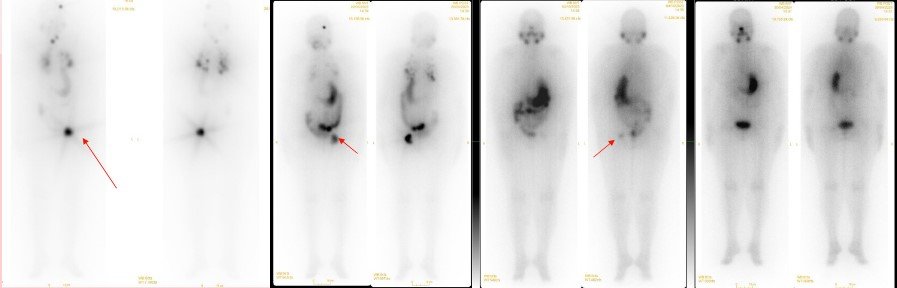

61y/ F total thyroidectomy and central neck dissection; post left femoral resection and endoprosthesis reconstruction on 01-07-22 HPE- residual follicular carcinoma in left lobe of thyroid, LN -ve; metastatic follicular carcinoma of thyroid